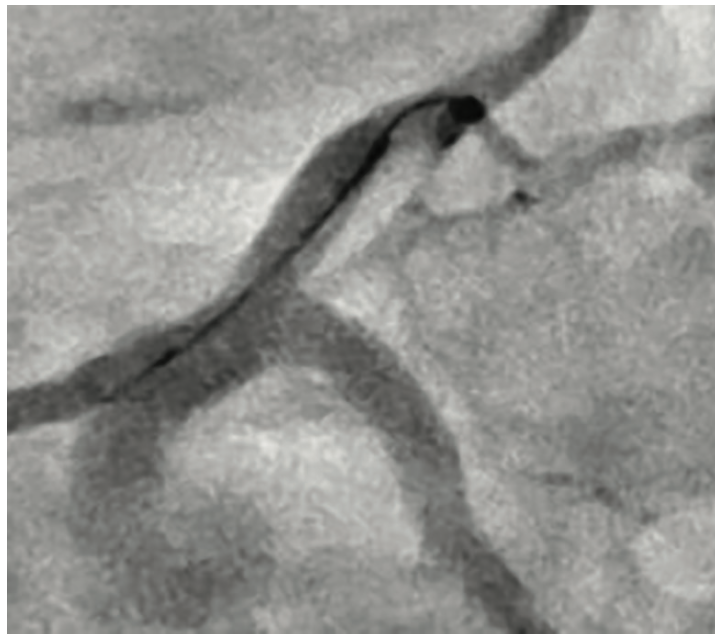

Right radial access was obtained with a radial 7 French (Fr), 10 cm length GLIDESHEATH SLENDER® Introducer Sheath (Terumo Interventional Systems) and the ostium of the LMCA was engaged with a 7 Fr Extra Backup (EBU) 3.5 guide catheter (Medtronic) to facilitate bifurcation stenting. The initial angiogram images revealed a worsening of the distal LMCA stenosis, now at 80% and extending into the ostial LAD (Figure 1). A Runthrough NS Izanai White guidewire was advanced across the lesion into the distal LAD and a Runthrough NS Izanai Blue was advanced across the lesion into the distal LCx with minimal difficulty. To facilitate intravascular ultrasound catheter delivery, the distal LMCA/ostial LCx was predilated with a semicompliant 2.0 mm x 15 mm Takeru PTCA Balloon Dilatation Catheter at nominal pressure (8 atmospheres). IVUS of the LCx was performed first, followed by IVUS of the LAD, and showed severe, concentric calcification of the distal LMCA and ostial LAD/LCx (Figure 2). For plaque modification and lesion optimization prior to stent deployment, a 3.5 mm x 12 mm C2+ intravascular lithotripsy balloon (IVL, Shockwave Medical) was advanced first into the LCx and subsequently into the LAD. The LMCA to proximal LCx and the ostial LAD were treated with 120 pulses with 12 inflations of the IVL balloon. Angiography revealed no evidence of dissection following IVL; however, there was some recoil in the ostial LCx, for which cutting balloon angioplasty was performed with a 3.5 mm x 15 mm Wolverine balloon (Boston Scientific) in the ostial LCx and extending back into the distal left main. Next, the decision was made to proceed with bifurcation stenting using a culotte strategy. A 3.5 mm x 20 mm Synergy Megatron drug-eluting stent (DES, Boston Scientific) was placed from the distal LMCA into the proximal LCx (Figure 3). Following post dilation of the DES with a 3.5 mm x 15 mm noncompliant balloon, a new Runthrough NS Izanai White was used to re-wire the LAD through a side strut of the LMCA-LCx DES. A semicompliant 3.0 mm x 12 mm Takeru PTCA Balloon Dilatation Catheter crossed into the LAD with minimal difficulty and was used to dilate the stent struts to facilitate delivery of the LMCA-LAD DES. A noncompliant 3.0 mm x 15 mm balloon inflation was performed to optimize the LAD lesion further. A 3.5 mm x 16 mm Synergy Megatron DES was then placed in the proximal LAD, overlapping with the prior stent in the LMCA (Figure 4). Following post dilation of the LMCA-LAD DES with a 3.5 mm x 15 mm noncompliant balloon, the proximal portion was optimized (proximal optimization technique [POT]) with a 4.0 mm x 8 mm noncompliant balloon. The LCx was then rewired with the Runthrough NS Izanai White through a side strut of the LMCA-LAD stent and the Runthrough NS Izanai Blue was placed in the LAD. Following serial dilations of the LMCA-LAD stent struts with Takeru PTCA Balloon Dilatation Catheters, kissing balloon inflation of both the LAD and LCx extending back into the LMCA was performed with a 3.5 mm x 15 mm noncompliant balloon in the LCx and a 3.0 mm x 15 mm noncompliant balloon in the LAD (Figure 5). Repeat IVUS of both stents back into the LMCA was performed, demonstrating adequately expanded and apposed stents with no evidence of edge dissection. Final POT was performed in the LMCA with a 4.5 mm x 8 mm noncompliant balloon. Final angiography revealed TIMI-III flow, no evidence of proximal or distal edge dissections, no perforation, and <5% residual stenosis (Figure 6). The total contrast volume was 55 mL with a case length of 1.5 hours. The patient was discharged three days later without complication.